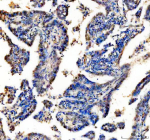

IHC analysis of RAD51D using anti-RAD51D antibody. RAD51D was detected in a paraffin-embedded section of human lung cancer tissue. Heat mediated antigen retrieval was performed in EDTA buffer (pH 8.0, epitope retrieval solution). The tissue section was blocked with 10% goat serum. The tissue section was then incubated with 2 ug/ml rabbit anti-RAD51D antibody overnight at 4oC. Peroxidase Conjugated Goat Anti-rabbit IgG was used as secondary antibody and incubated for 30 minutes at 37oC. The tissue section was developed using an HRP secondary and DAB substrate.